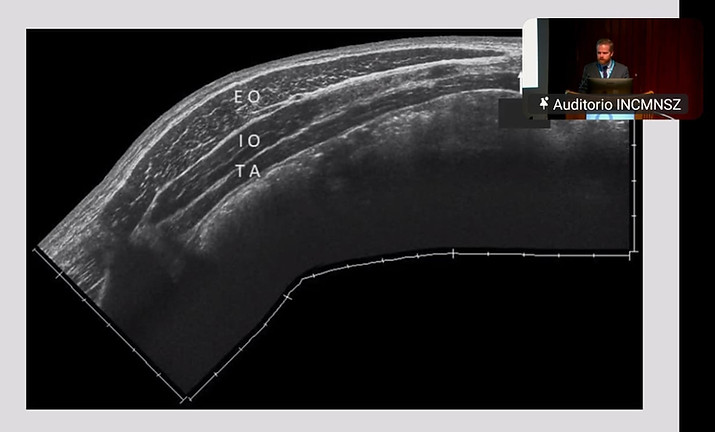

1. Estudios de imagen en pacientes con problemas de pared abdominal.

Dr. Luis Fernández Vázquez Mellado

9.Anatomía quirúrgica del músculo transverso del abdomen.

Dr. Gabriel Arévalo